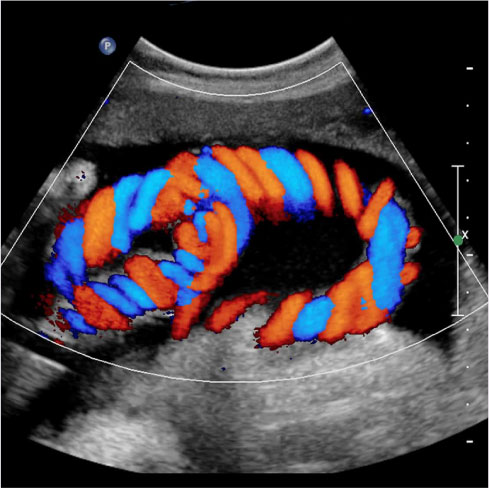

The Colour Doppler test is a diagnostic technique that creates an image from sound waves. It provides information about the speed, movement and direction of blood flow. our doctors will use this test to check for blockages and clots in your blood vessels. This is not possible with conventional ultrasonography as it fails to show blood flow. In the colour doppler test, no dye is injected into your body. Thus, making this a safe and convenient test. The colour doppler test is based on the Doppler effect. This test measures the sound waves reflected from moving objects like red blood cells to create images of blood flow.Nexsus Plus Diagnostic Centre is the Best Color Doppler Test Centre In Navi Mumbai Providing various imaging services such as 3d,2d Sonography centre,Color Doppler Test

A Doppler ultrasound is a noninvasive test that can be used to estimate the blood flow through your blood vessels by bouncing high-frequency sound waves (ultrasound) off circulating red blood cells. A regular ultrasound uses sound waves to produce images, but can't show blood flow.

A Doppler ultrasound, also called a Color Doppler test is a non-invasive test that can be used to estimate your blood flow through blood vessels. It helps doctors evaluate blood flow through major arteries and veins, such as those of the arms, legs, and neck. It can show blocked or reduced flow of blood through narrow areas in the major arteries of the neck that could cause a stroke. It also can reveal blood clots in leg veins (deep vein thrombosis, or DVT) that could break loose and block blood flow to the lungs (pulmonary embolism). During pregnancy, Doppler ultrasound may be used to look at blood flow in an unborn baby (foetus) to check the health of the foetus.If Your Doctor is suspecting Blockages in the arteries,the presence of blood clots or other health conditions.Then one should always visit the Best Color Doppler Test Centre in Navi Mumbai

Abdominal ultrasound with Color Doppler is an imaging procedure that uses sound waves to create images of abdominal organs as well as blood flow within them. The Color Doppler ultrasound of the abdomen allows visualization of blood flow in real-time.

During an abdominal ultrasound with color Dopplera small handheld device called a transducer is placed on the skin of the abdomen and moved over the area of interest. The ultrasound probe sends high-frequency sound waves into the body, which bounce off the organs and tissues and create echoes. These echoes are detected by the transducer and used to create images of the internal structures of the abdomen.

Color Doppler imaging is used to evaluate blood flow in the abdominal organs in addition to conventional ultrasound imaging. It utilizes a variety guide to show the speed and course of blood stream inside the vessels. Abnormalities like blockages, narrowing of blood vessels, or patterns of abnormal blood flow can all be identified with the assistance of this information. A variety of abdominal conditions, such as Liver Disease, Gallstones, kidney disease, and abdominal aortic aneurysm, can be evaluated with color Doppler abdominal ultrasound. It is a safe, harmless, and effortless system that doesn't utilize ionizing radiation and commonly requires 30-an hour to finish.